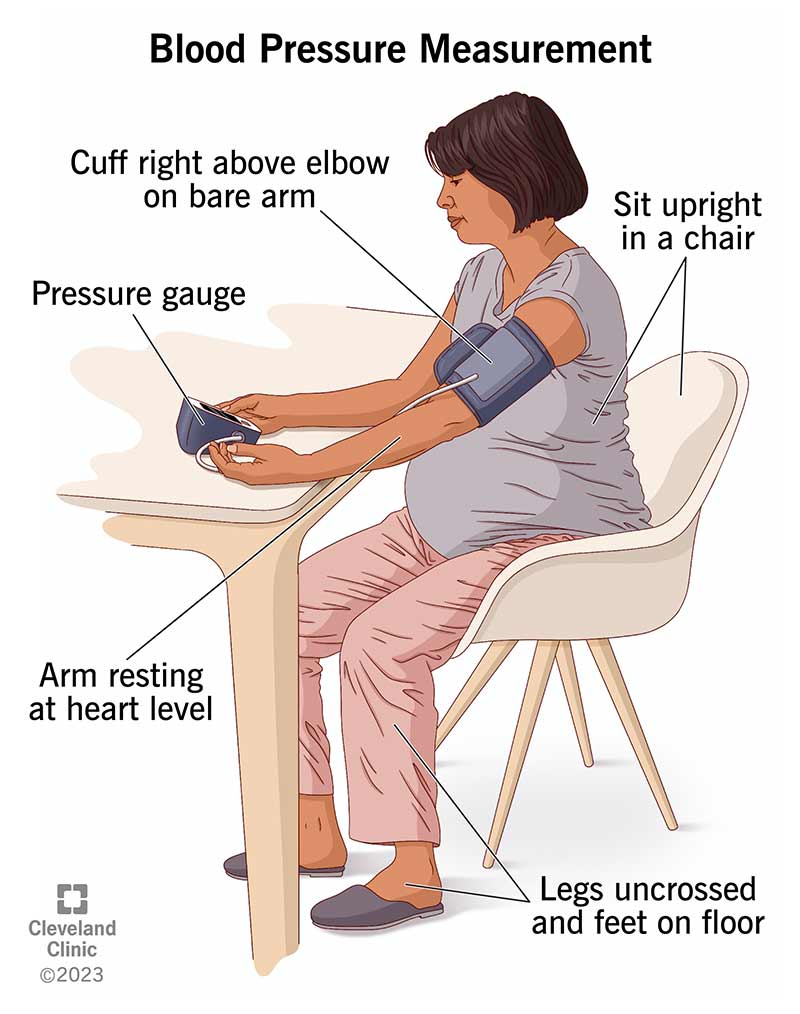

How To Measure Blood Pressure Without Equipment Store

https://my.clevelandclinic.org/-/scassets/images/org/health/articles/25068-blood-pressure-measurement-illustration